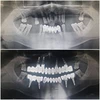

Klinik çalışmalarını İmplant ve Estetik diş hekimliği uygulamaları konusunda yoğunlaştırmıştır.

Periimplantitis

Peri-İmplant Mukozitis

Implant tedavisi